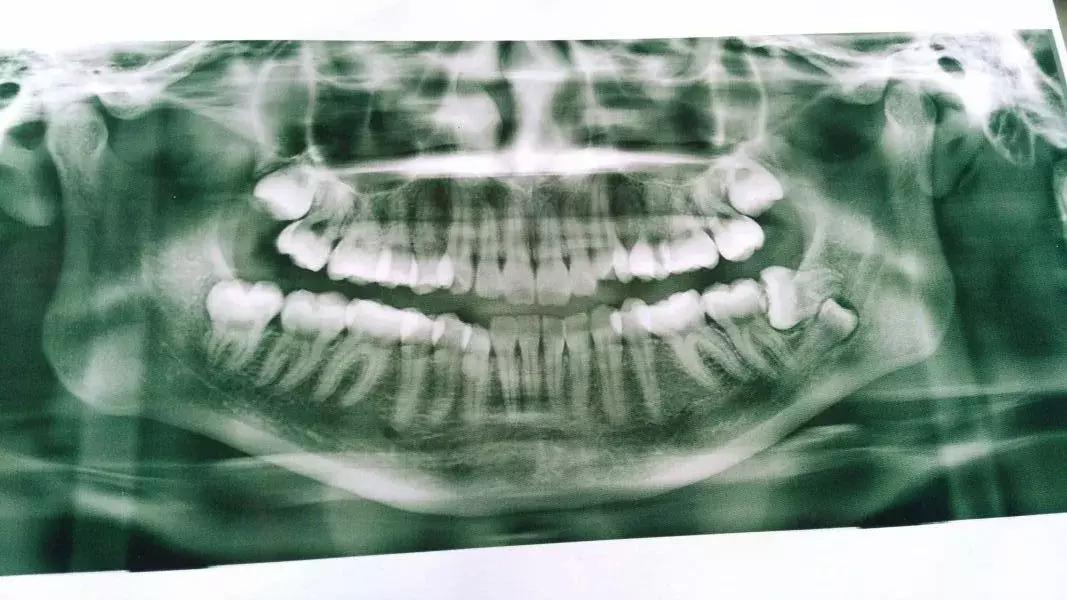

那今天就走写实风了,都真牙真嘴真牙片,欢迎大家拿着自己牙片对号入座下,看清智齿的真面目后,最好能治治大家的拔牙拖延症。

附上几个带牙片诊断

1、长成这样的智齿需要拔吗?

你的左下智齿是完全埋伏的阻生齿,在确定没有实质的危害的情况下可以不拔。什么叫实质的危害呢?比如,是不是顶到了前牙,引起了左下7的牙根吸收?比如,有没有产生了含牙囊肿?比如有没有产生了你无法忍受的症状——主观或客观?怎么看?拍 CBCT 看。一张曲面断层片看到的信息是不够的。如果 CBCT 显示没有左下 7 牙根吸收、没有含牙囊肿等等,就先留着吧。

3、水平阻生的智齿必须拔吗?

如果大于25岁,且从未发炎,CT显示并未威胁到邻牙,可长期观察

5、这种情况咋回事?要拔吗?

智齿下面的牙齿是下颌双尖牙异位了,位置很深,需要定期密切观察。和智齿一起拔的话,骨折风险不低。即便拔,建议拍个CBCT,住院拔。